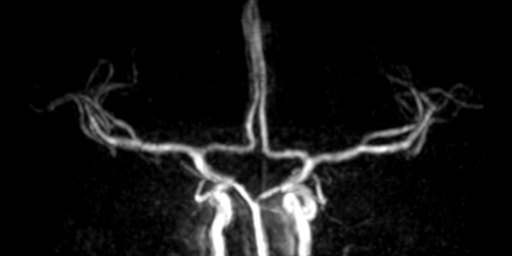

La seconda soluzione che ho trovato (e che pensavo sarebbe uscita molto peggio) é una Angio Phase Contrast che in effetti, non utilizzando l’effetto inflow, é venuta discretamente bene ed ha permesso di visualizzare un buon numero di vasi. Metto qui sotto l’immagine finale

Col senno di poi, visto come é venuta, avrei potuto dedicarci più tempo per una miglior risoluzione spaziale e maggior copertura H-F. In ogni caso la paziente tornerà per rifare l’esame dopo aver tolto l’apparecchio.